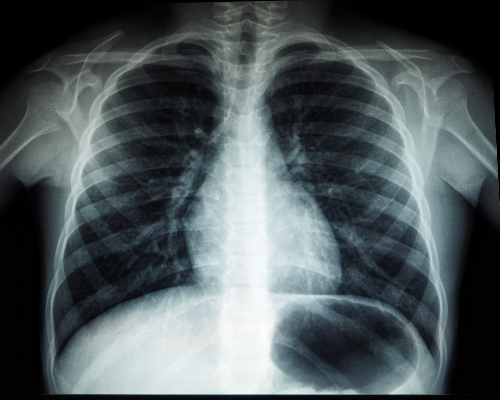

3.CT(전산화 단층촬영)

흉부 CT 촬영은 흉부 엑스레이보다 폐암을 발견할 수 있는 확률이 높고 이로 인해 폐암을 조기 발견하여 사망률은 낮출 수 있습니다. 저선량 CT는 방사선 조사량을 기존 CT에 비해 현저하게 줄이는 검사 방법으로 방사선에 노출되는 위험을 줄일 수 있습니다. 이 검사 방법은 해상도는 저선량이라서 기존 CT에 비하여 감소하지만 병변 유무를 관찰하는 데는 충분하며 간편한 검사입니다. X-ray에서 발견이 어려운 초기 폐암의 경우 흉부 CT 촬영을 통해 조기에 발견할 수 있습니다.